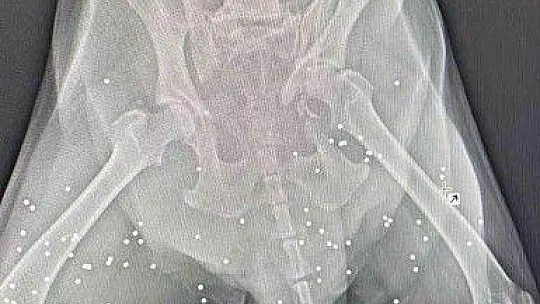

Muğla'nın Bodrum ilçesinde trafik kazası sonucu yaralanan köpeğin çekilen röntgen filminde, daha önce tüfekle vurulduğu ve vücudundaki saçmalarla yaşadığı ortaya çıktı.

Araç çarpması nedeniyle kalçasında kırık olan köpeğin vücudunda onlarca saçmaya rastlandı. Saçmalar, hayvanın daha önce tüfekle vurulduğunu ve vücudunda saçmalarla yaşadığını ortaya çıkardı. Köpeğin ne zaman vurulup ne zamandan beri vücudunda saçmalarla yaşadığı bilinmiyor. Hayvanın tedavisinin özel bir veteriner kliniğinde sürdüğü öğrenildi.